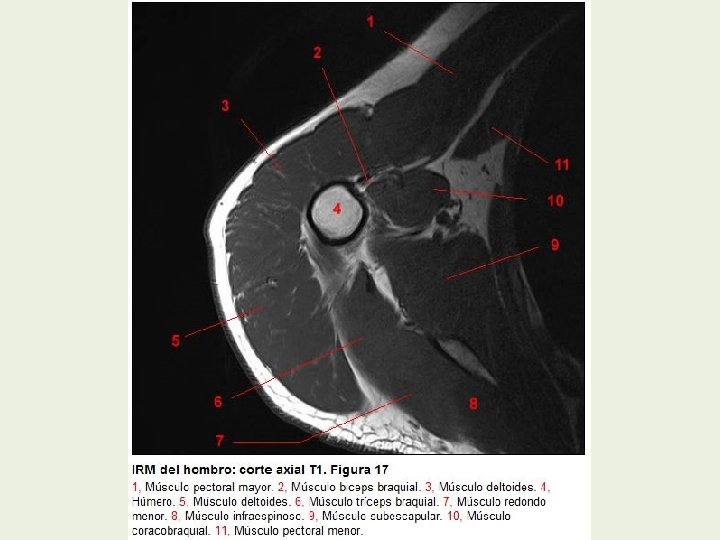

Hombro Cortes axiales RMN